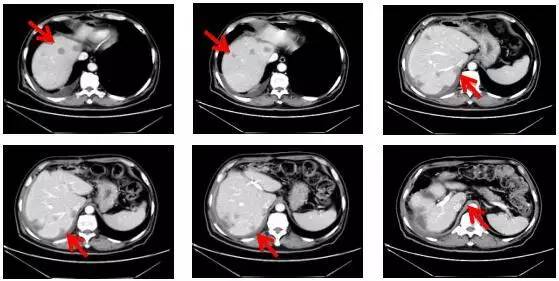

男性患者,70岁,于2015年5月因“便血2年余”发现直肠癌并肝转移,并先后接受直肠癌切除和肝肿瘤切除手术。术后40天患者肝内新发多个转移病灶。至此,病人的预期生存平均不超过1年。

为求得规范的高水平治疗,病人求医于王潍博教授并入住化疗科。在王潍博主任主持下,化疗科对该病例进行了讨论研究,决定予以全身化疗、分子靶向治疗和微创治疗相结合的肿瘤综合治疗。讨论决定予结肠癌经典化疗方案mFOLFOX6,同时联合的分子靶向治疗药物贝伐珠单抗。

经上述方案治疗6个周期以后,肝脏肿瘤已经明显缩小。经化疗科再次讨论,决定加行肝转移瘤微波消融术,以期尽量消除残存病灶。2015年12月8日,在王潍博主持下,化疗科医生郑爱民副主任医师对该病例肝内病灶成功进行了消融治疗。

患者治疗前肝转移情况

经过靶向治疗联合化疗,患者病灶缩小

2015.7.3

2015.9.4

2015.12.4